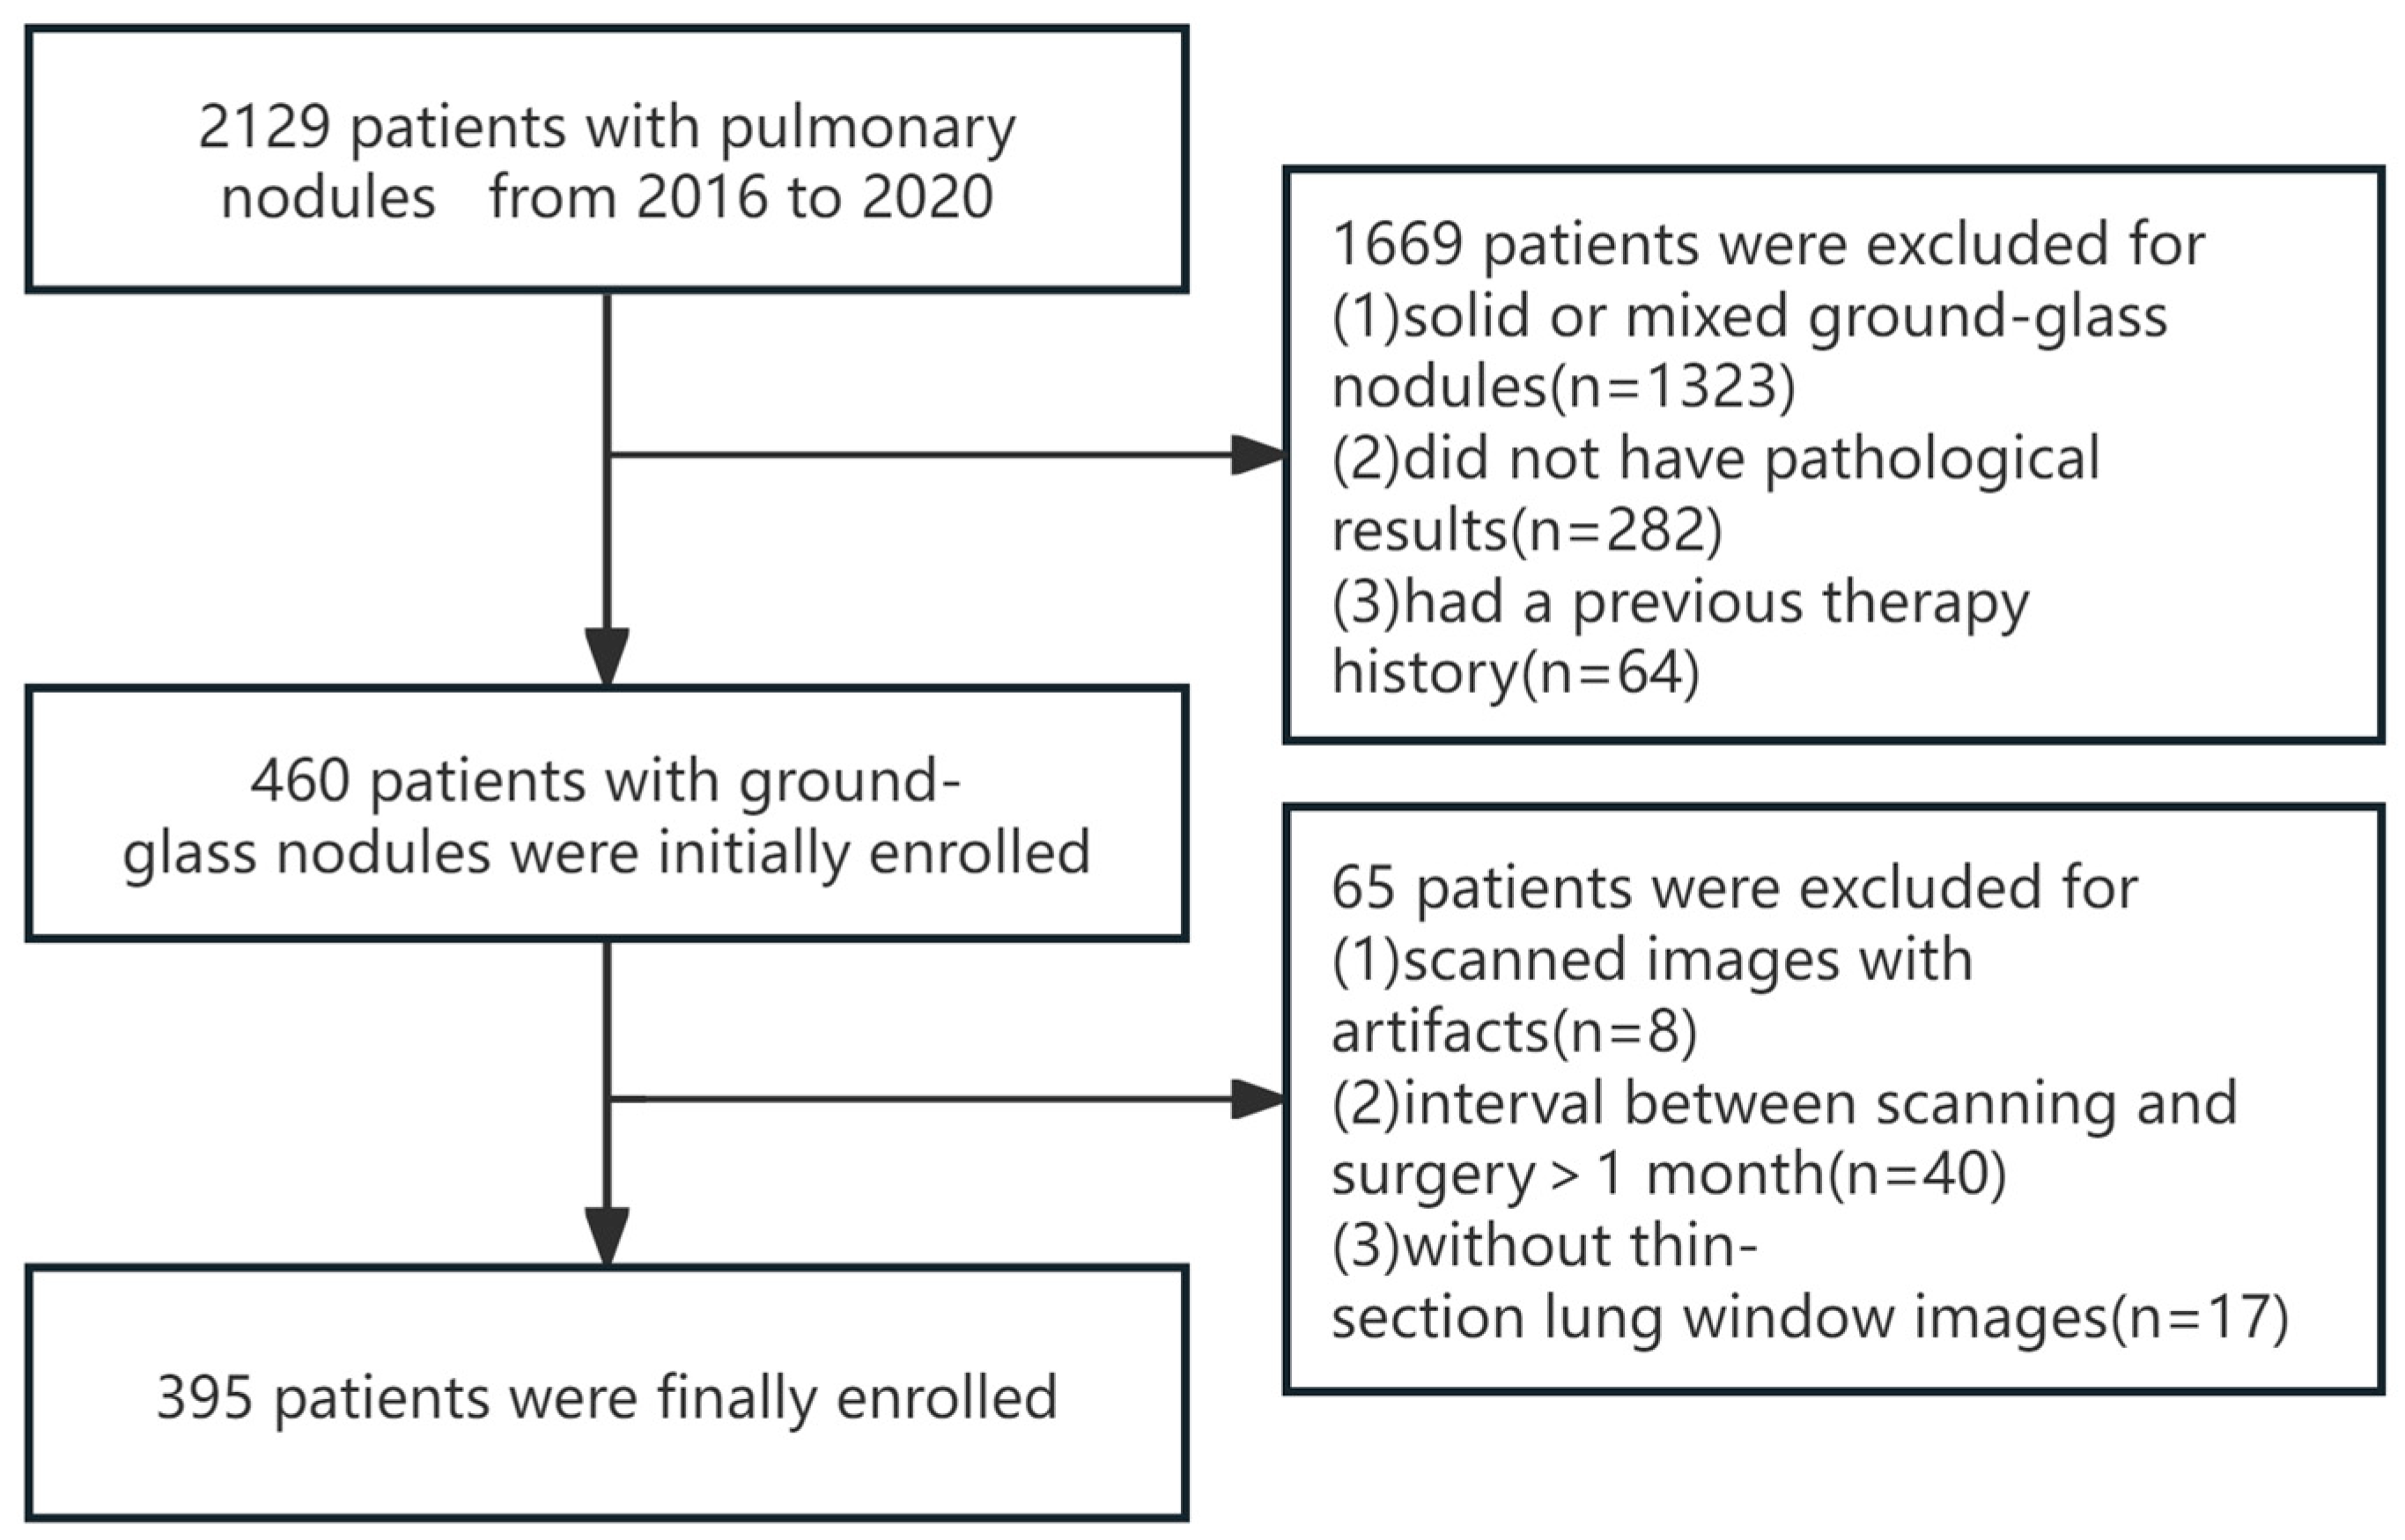

2.1. Study Population